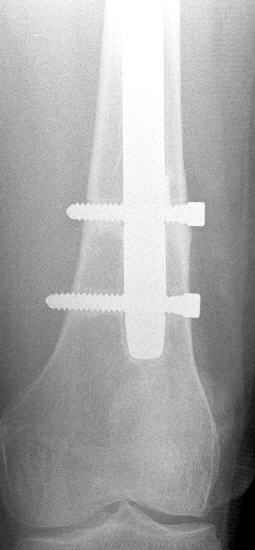

May I have some advice on the following case? Middle aged woman, No chronic medical problems, +tobacco use - but she promises she's going to quit! Original MVC in late 1990's, initial rod failed, and 2 subsequent exchanges failed (most recently shown in attached jpgs.)

Most recent one (6/2002) was apparently an open nailing to remove last broken nail, but no grafting was performed in conjunction. Now sent to me with broken 14mm R/T nail in place.WBC, Hgb, Chemistries normal.ESR 34CRP 4.2No other apparent locus of infection.I was considering a staged approach - removing nail and screws and obtaining cultures.If negative, proceed with exchange nailing with open grafting +/- BMP, But how best to deal with that pedestal distally and avoid anterior breech near patella? If positive cultures, what would be best option?Thanks. Tom Schaller Kalamazoo, MI.

In my opinion, there is no nail strong enough to tolerate a varus deformity of femur after nailing. The AP view of the distal femur shows that the femur has been repeatedly nailed in varus. The tip of the nail is short and lateral in distal lateral metaphysis. It should be central over the intercondylar notch and buried in the distal epiphyseal scar. This has resulted in constant bending forces on the nail (see the "windshield wiper" sign) and its eventual fatigue failure.